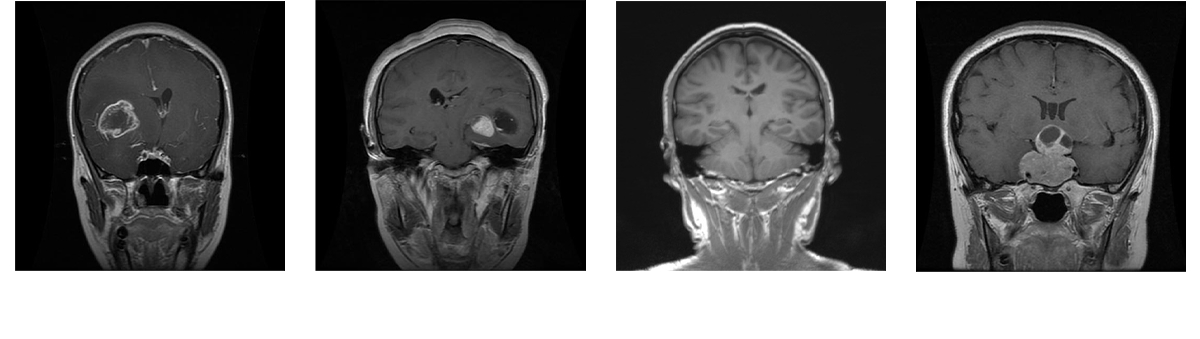

Brain tumors are among the deadliest diseases in the world. Magnetic Resonance Imaging (MRI) is one of the most effective ways to detect brain tumors. Accurate detection of brain tumors based on MRI scans is critical, as it can potentially save many lives and facilitate better decision-making at the early stages of the disease. Within our paper, four different types of MRI-based images have been collected from the database: glioma tumor, no tumor, pituitary tumor, and meningioma tumor. Our study focuses on making predictions for brain tumor classification. Five models, including four pre-trained models (MobileNet, EfficientNet-B0, ResNet-18, and VGG16) and one new model, MobileNet-BT, have been proposed for this study.